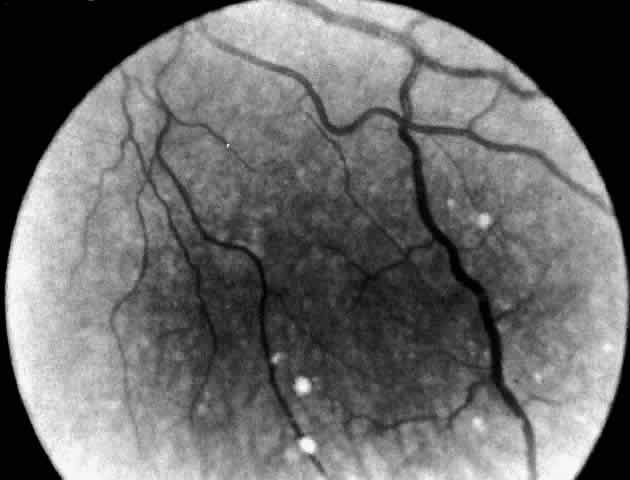

A more widespread opacification of the retina can occur due to involvement of the ganglion cells in the posterior pole. This was observed by Wray4 in a 3½-year-old child with Tay-Sachs disease. The child had black hair and brown eyes, and the cherry-red spot at the macula was brown. The patient was blind, with marked optic atrophy (Fig. 4).

Fig. 4. Fundus of 3 1/2-year-old girl with Tay-Sachs disease. Note cherry-red spot, an extensive white parafoveal halo, and optic atrophy.